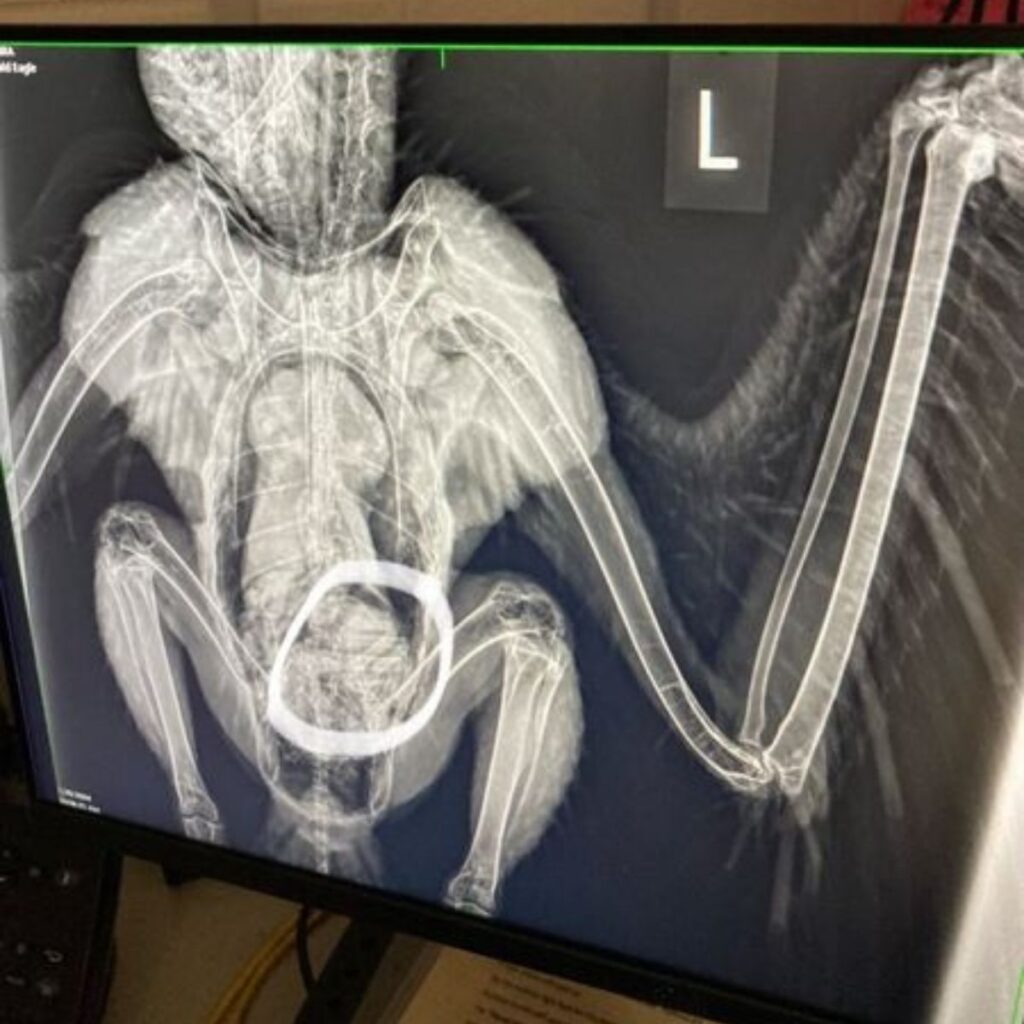

To get answers, the bird was taken to Dickerson Park Zoo for X-rays. That’s when the mystery was solved, and the entire team burst out laughing.

The x-ray showed something unmistakable: the paws of a raccoon sitting inside his very full stomach. The bird had indulged in such an oversized meal that flying was out of the question.